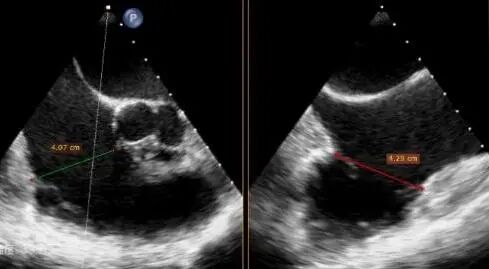

Preoperative CT: Tricuspid annulus: circumference 15.6 cm, area 18.8 cm², maximum diameter 53.2 mm, septolateral diameter 48 mm, anteroposterior diameter 51 mm.

Comparison of Tricuspid Annular Area After Annuloplasty

Preoperative tricuspid annular area: 15.6 cm²

Postoperative tricuspid annular area: 7.68 cm²

Following annuloplasty, leaflet coaptation was improved compared with the preoperative state, and regurgitation was reduced from severe to trivial.